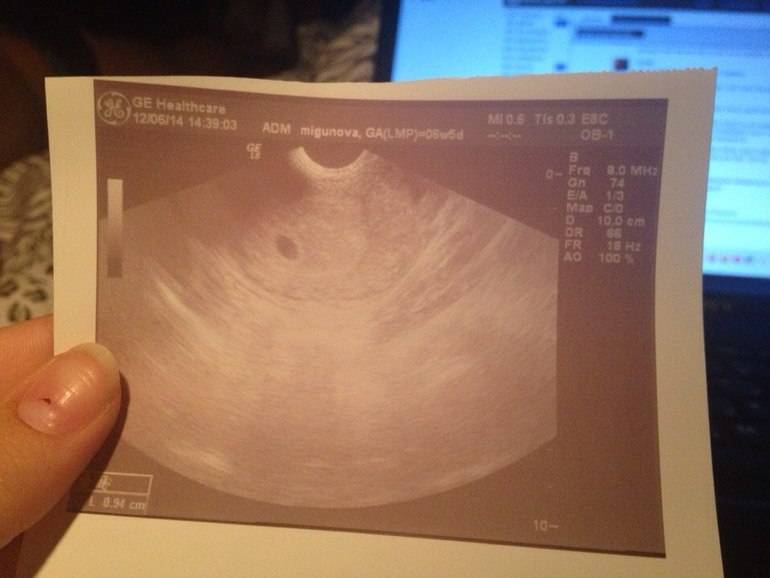

УЗИ двухплодной беременности на 5 неделе: Подборка изображений

Раздел: Калейдоскоп образов